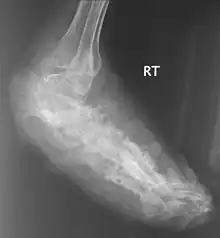

X rays and ultrasonography may be carried out to assess the extent of the disease. X rays findings are extremely variable. The disease is most often observed at an advanced stage that exhibits extensive destruction of all bones of the foot. Rarely, a single lesion may be seen in the tibia where the picture is identical with chronic osteomyelitis. Cytology of fine needle aspirate or pus from the lesion, and tissue biopsy may be undertaken sometimes.[11] Some publications have claimed a "dot in a circle sign" as a characteristic MRI feature for this condition (this feature has also been described on ultrasound).[14]

Madura Foot X-Ray